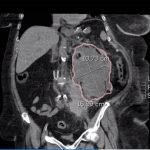

Bedside ultrasound was performed and demonstrated a hypoechoic area within the left kidney (images not shown). The non-contrast computed tomography (CT) of the abdomen and pelvis shows a significantly enlarged left kidney and a region of high-attenuation encapsulating the left kidney, concerning for acute hemorrhage.